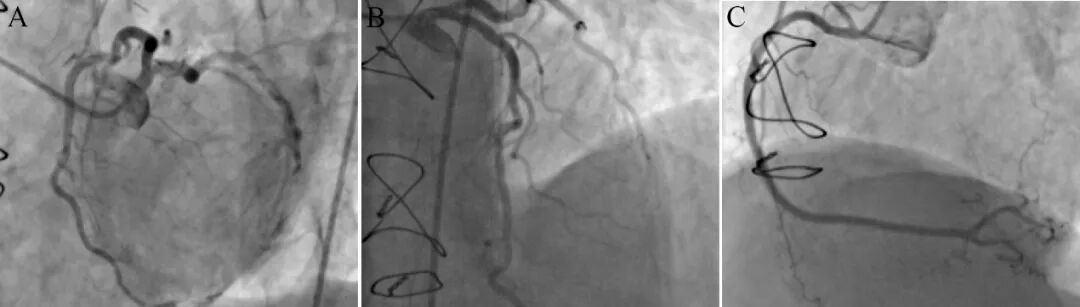

冠脉造影示三支冠脉无狭窄(图2),LIMA桥血管纤细。对比10年前造影,开口狭窄几乎消失(图3)!最合理的解释是,原先狭窄为导管诱发冠脉开口严重痉挛!出院加用贝尼地平抗痉挛治疗,未有胸闷再发。

图2 10年后冠状动脉造影显示三支基本正常

图3 两次造影图像对比,箭头示狭窄部位